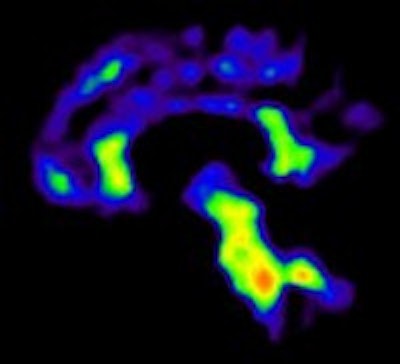

In recent years, both FDG and PiB have become more prominent biomarkers in the diagnosis of several forms of dementia, Ossenkoppele noted. PiB is designed to detect deposits of amyloid plaque in the brain, which have been associated with the onset of Alzheimer's disease. FDG measures metabolic activity of the brain at rest and has been used to distinguish between several forms of dementia.

Researchers then proceeded to the PET scans. First, patients were imaged with PiB for 90 minutes to obtain parametric images of the biomarker binding to potential clusters of amyloid. FDG-PET scans were then conducted 45 to 60 minutes after injection and lasted for 15 minutes. Standardized uptake value (SUV) ratios were calculated throughout the brain.

In the Alzheimer's group, PET with PiB or FDG confirmed a total of 44 (67%) of the 66 cases prior to PET imaging. The second-greatest change was among patients with frontotemporal dementia. PET with PiB or FDG confirmed 11 (61%) of the 18 cases prior to PET.

PiB-PET scans were positive in 40 (61%) of 66 patients with clinical Alzheimer's and in five (28%) of 18 patients with clinical frontotemporal dementia. FDG SUV patterns matched the clinical diagnosis in 58% of patients with Alzheimer's and 33% of patients with clinical frontotemporal dementia, the authors noted.

The researchers found a "frequent mismatch between clinical diagnosis and PET findings," Ossenkoppele said. "PiB and FDG led to a diagnostic change in almost one out of four patients [and] increased the diagnostic confidence, and PiB and FDG seem most useful when diagnostic confidence is low," he concluded.